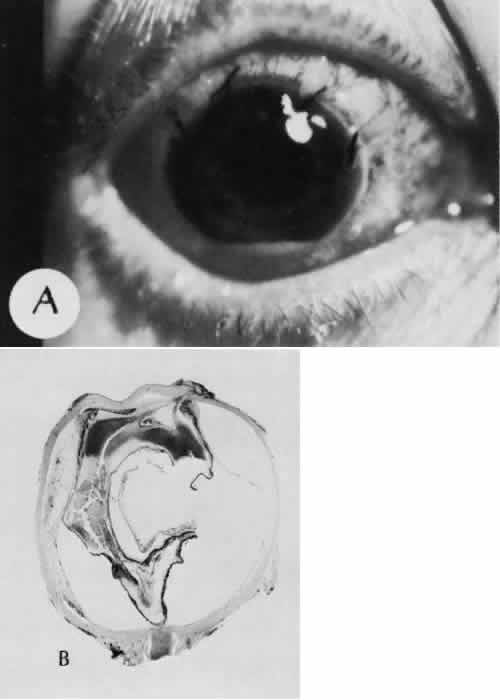

| All ocular surgical procedures are associated with potential complications. A